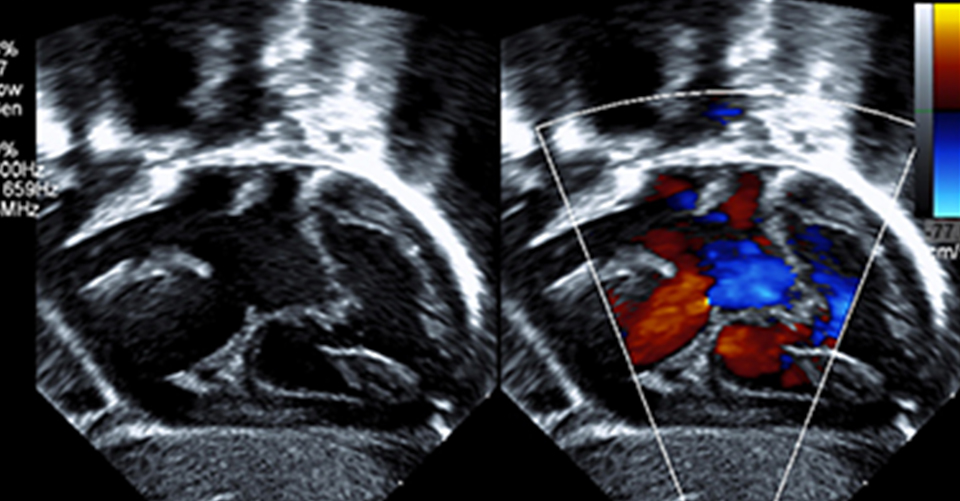

Common Heart Conditions in Children

Heart diseases are hard to deal with for full-grown adults. When these diseases affect children, it...

5 Common Childhood Heart Defects Every Parent Should Know About

Here’s a handy guide on common pediatric cardiac problems  Whether you’re expecting a baby,...